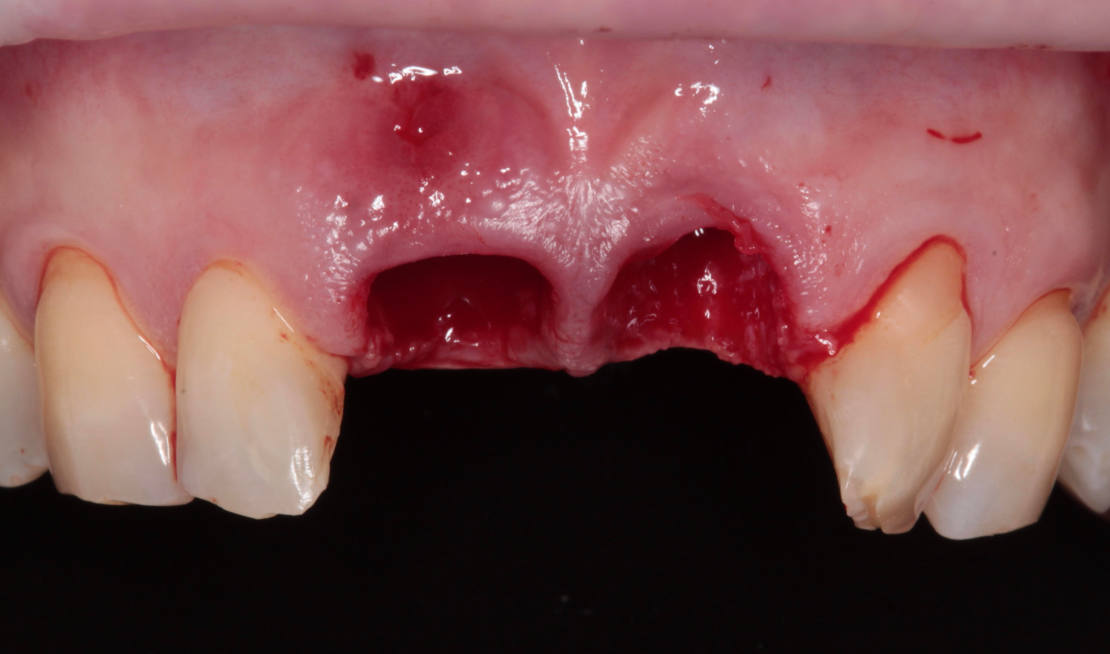

Vďaka týmto postupom bola operácia veľmi rýchla a pacientka odišla z ordinácie plne rehabilitovaná. Minimálne invazívnym spôsobom boli extrahované horné jednotky (obr. 6).

Následne sme použili protokol vŕtania a zavedenia implantátov cez šablónu (obr. 7, 8), na ktorej sme mali orientačné body pre správne napolohovanie implantátov, abutmentov a koruniek (obr. 9–14).